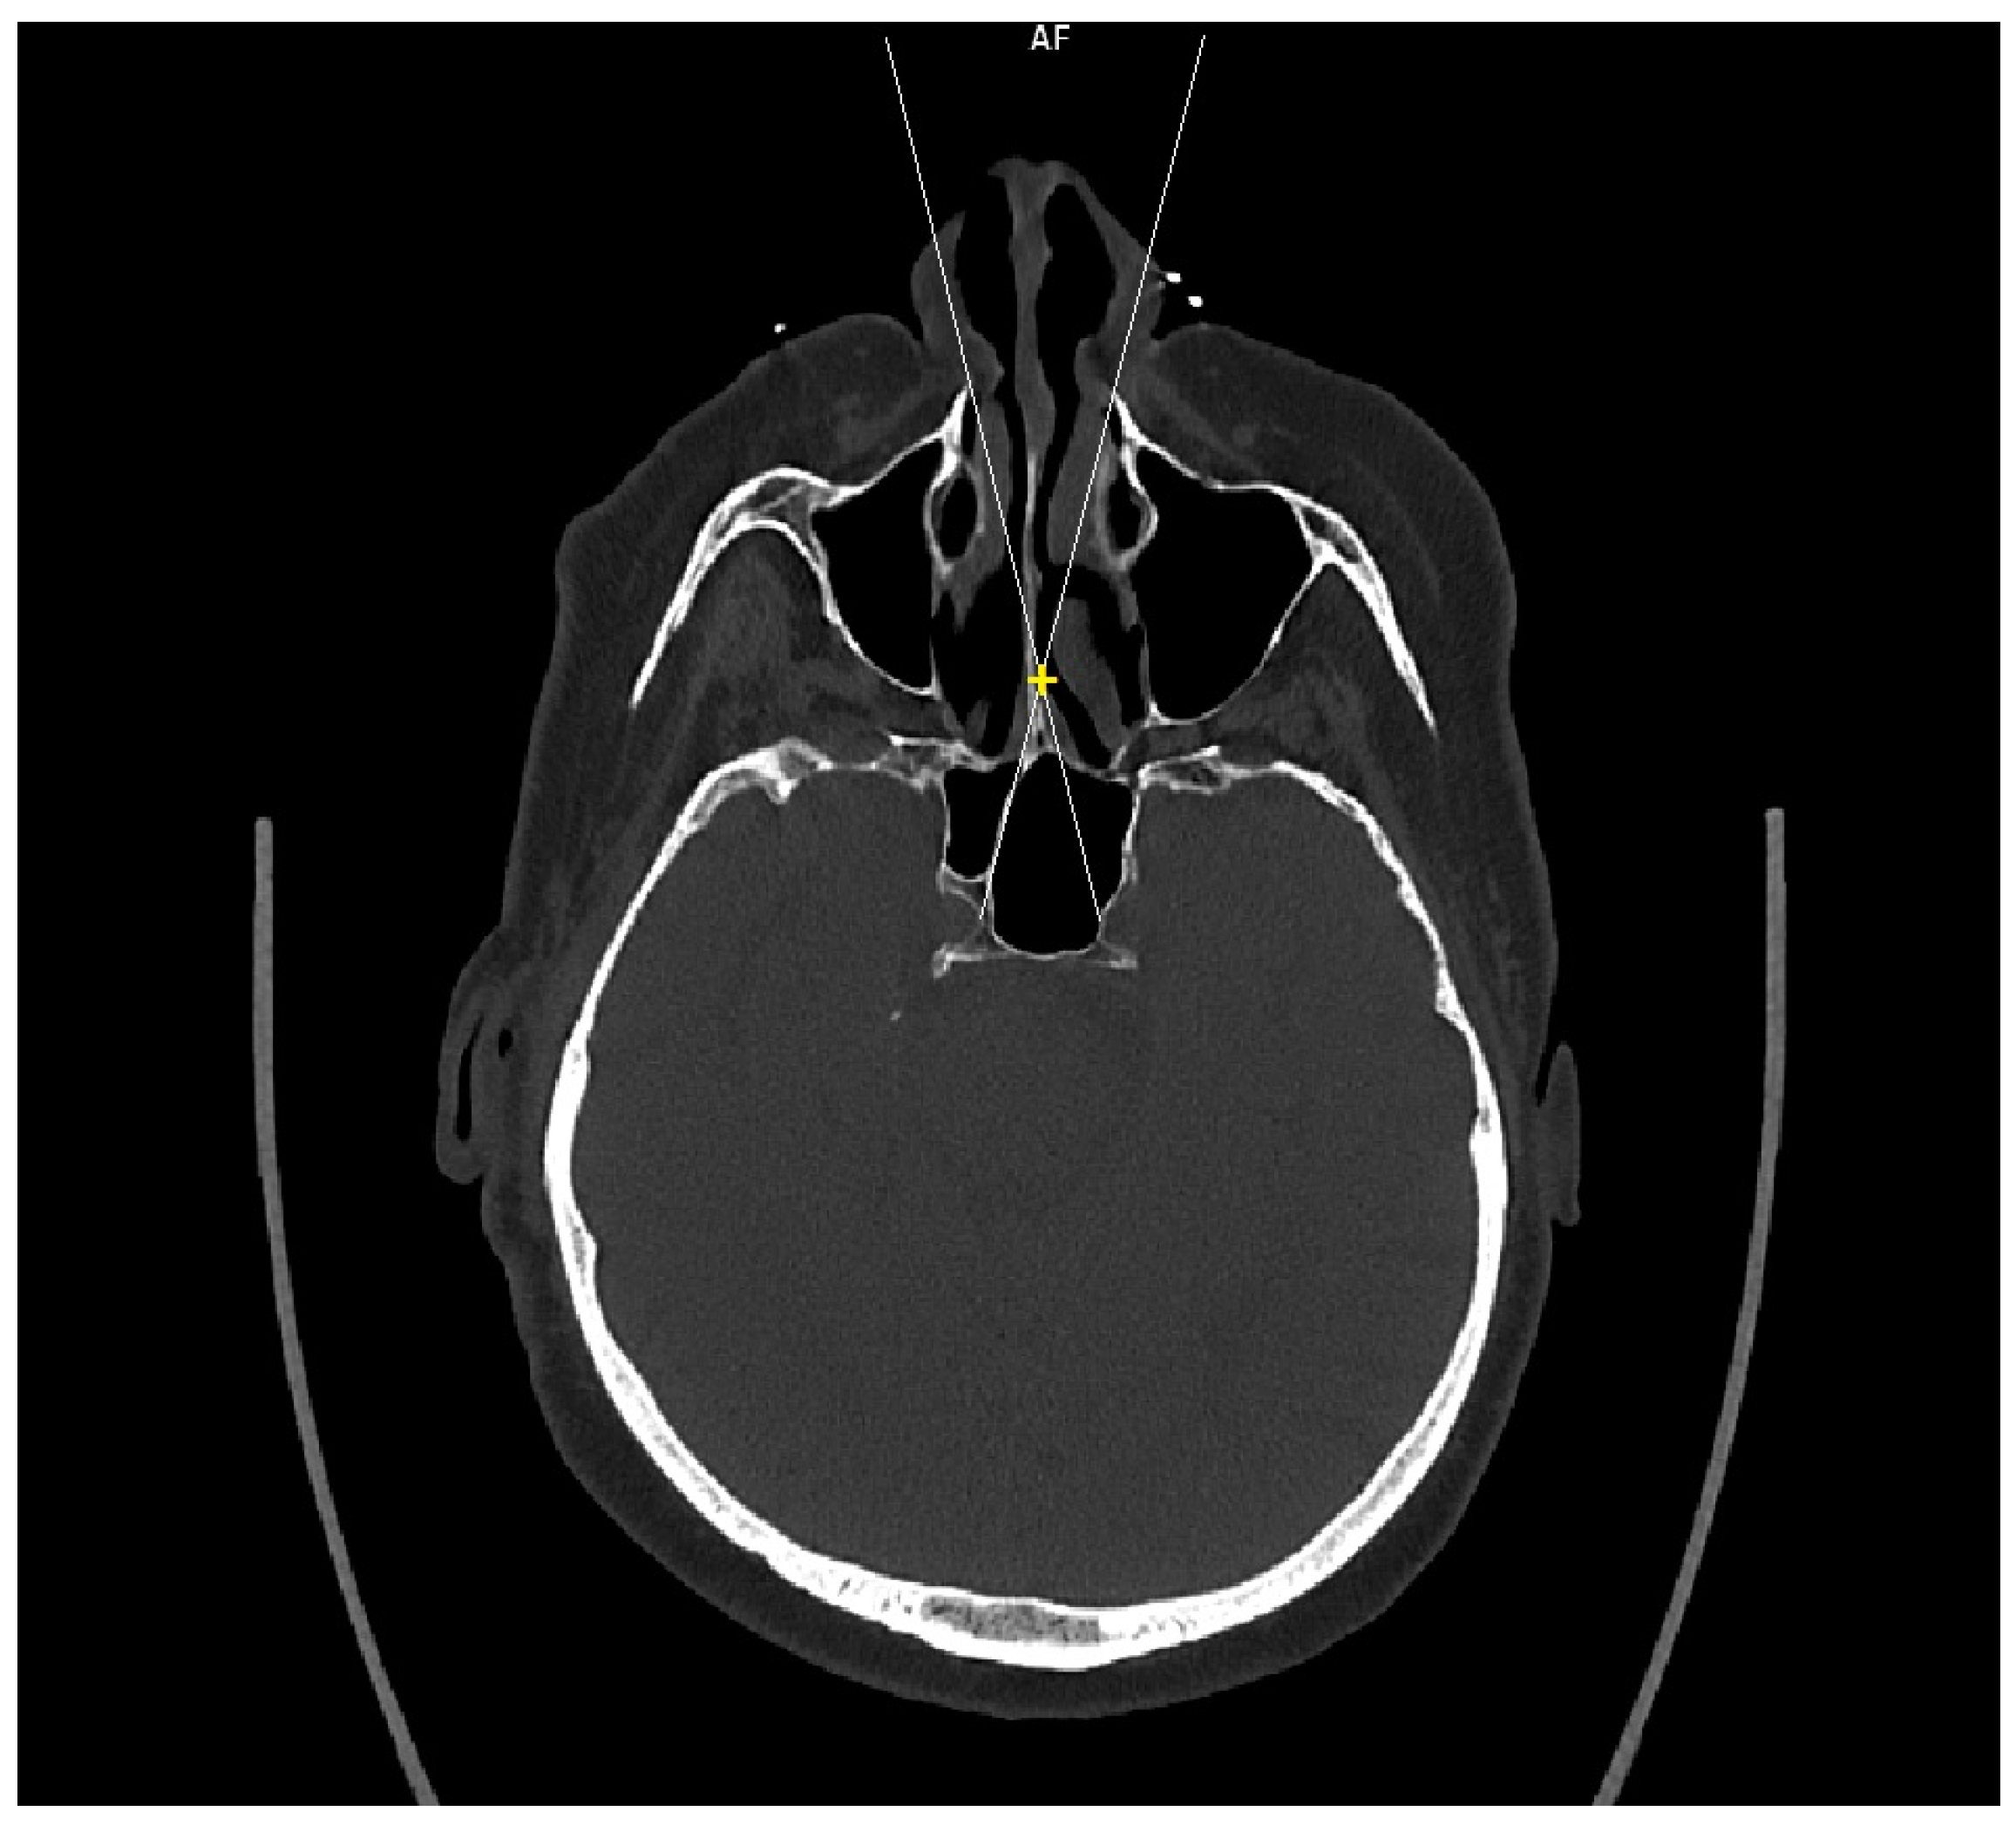

Patient CT scan: Preoperative CT scans from 20 patients with a pituitary adenoma were used for this study. The CT scans were performed on a Siemens Somatom force scanner (Siemens healthineers, Praha, Czech Republic). The measurement was performed with the SyngoVia program, using HrCT images with a slice thickness of 0.6 mm. In each patient, the semi-axial plane was created using multiplanar reconstruction by changing the angle of the axial plane to match the virtual insertion of a straight instrument during surgery through the left nasal cavity into the sphenoid cavity. The defined points for this semi-axial plane were spina nasalis anterior and dorsum sellae (Figure 1). In this semi-axial plane, at the height of the dorsum sellae, the following diameters were measured: the depth of the sphenoid cavity, the distance between the medial edges of the internal carotid arteries (ICA), the width of the pyriform aperture, and the width of the nasal cavity at the level of the attachments of the lower turbinates. The volume of the sphenoid cavity was measured with Fotom software (FOTOM 08 Plus, Ostrava, Czech Republic). Simulation of the virtual insertion of the two straight suctions (one in each nostril) was conducted in a semi-axial view at the height of the dorsum sellae. Instruments were represented with a straight white line; defined points for this white line were the lateral bony edge of the nasal aperture and the medial edge of the ICA. The intersection of the embedded virtual straight instruments (white lines) was marked with a yellow cross. The minimum septal resection required to reach the medial border of the ICA with a straightforward instrument was determined as the distance between the marked yellow cross and the anterior wall of the sphenoid cavity (Figure 2).

Figure 2. CT scan, semiaxial view, virtual straight instruments inserted into the sphenoid cavity to reach medial edge of the ICAs simulating binostril approach (white lines), crossing of virtual instruments simulating minimal septal resection needed to reach medial edge of the ICAs (yellow cross).